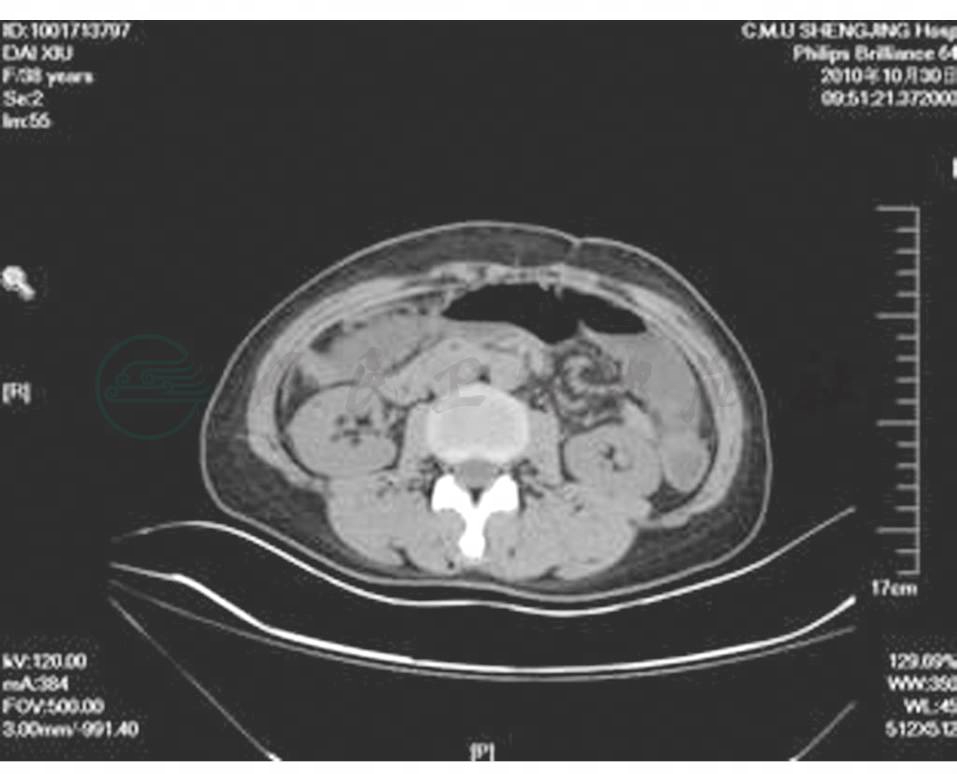

盆腔CT(2008-9-15):提示右侧会阴部良性肿物可能性大,前庭大腺囊肿?盆腔少量积液(图2)。

图2 盆腔CT